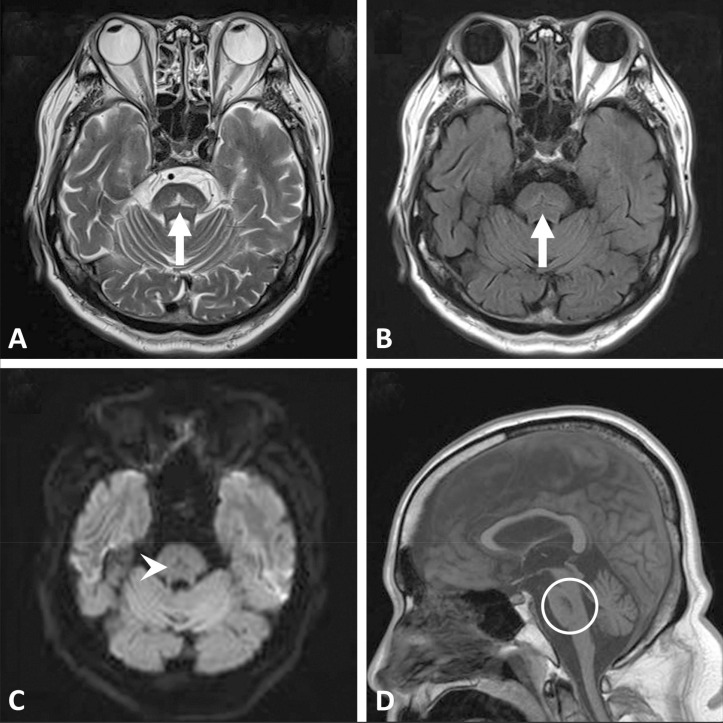

Hyponatremia is a common electrolyte disorder requiring careful management to prevent severe complications. Osmotic demyelination syndrome (ODS) is a serious neurological disorder that can develop from rapid correction of hyponatremia. Herein, is a description of the case of a 61-year-old man with multiple risk factors, including alcoholism, hypokalemia, malnutrition, and alcoholic liver cirrhosis, who developed ODS despite adherence to the recommended correction rate for hyponatremia. The patient presented to the emergency department with generalized weakness, gait disturbance, and decreased muscle strength. Initial laboratory investigations revealed severe hyponatremia, hypokalemia, and dehydration. The patient was treated with cautious correction of the hyponatremia below 8 mmol/L per day. However, on the seventh hospital day, he developed tremors, rigidity, and decreased consciousness and was diagnosed with osmotic demyelination syndrome. Despite receiving general supportive care, desmopressin, and dextrose 5% in water to reduce the serum sodium levels, the patient did not show significant improvement and was transferred to a nursing home for long-term conservative care on day 35 of hospitalization. This case report highlights the challenges associated with the diagnosis and management of osmotic demyelination syndrome and the importance of identifying patients at high risk of developing this neurological disorder.

Abstract Image